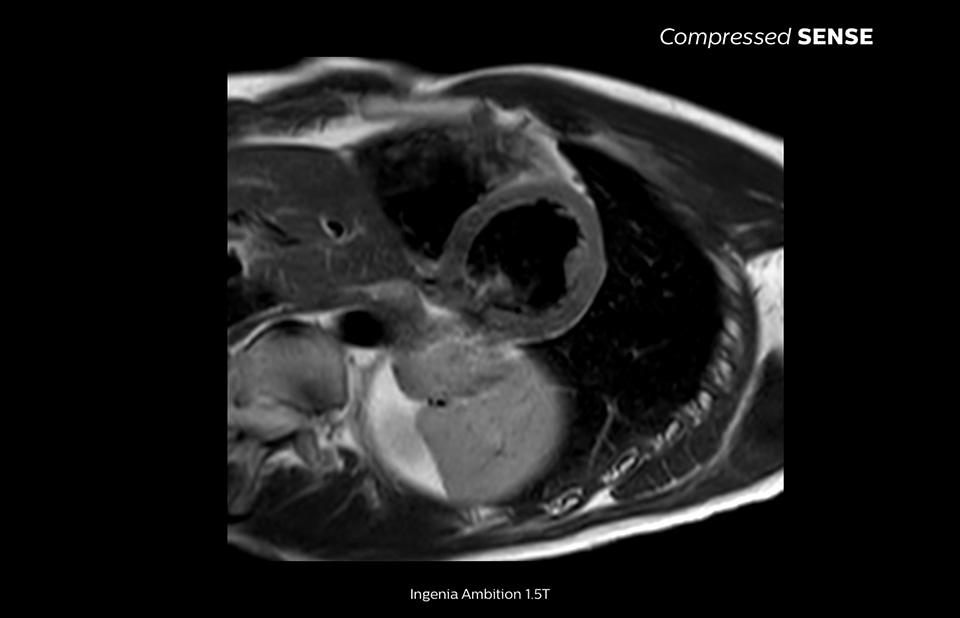

Philips Compressed SENSE verkürzt die Zeit, die ein Patient im MR-Scanner verbringt. Außerdem kann mit Compressed SENSE die Atemanhaltezeit verkürzt werden, was die Patientencompliance bei einem MR-Scan fördert.

4,8 s Atemanhalten

Da kurze Atemanhaltephasen einfacher für unsere Patienten sind, kommt es jetzt fast nicht mehr vor, dass Patienten den Atem nicht lang genug anhalten. In unserer Einrichtung sind bei Kardio-MRTs jetzt weniger Atemanhaltephasen nötig, oder die nötige Dauer der Atemanhaltephasen hat sich verkürzt.“

Dr. Takashi Koyama, MD, PhD, diagnostischer Radiologe und Leiter des Radiologiezentrums und der diagnostischen Radiologie, Kurashiki Zentralkrankenhaus, Japan

Eine Atemanhaltephase von 15 bis 16 Sekunden ist für viele Herzpatienten schwierig. Mit Compressed SENSE haben wir jetzt Protokolle, in denen diese Zeit auf unter 10 Sekunden reduziert wurde. Das ist für die Patienten viel einfacher. Die Patienten sind dann mit dem Verfahren auch viel zufriedener.“

Trevor Andrews, Ph.D., MR-Physiker, University of Vermont Medical Center, USA